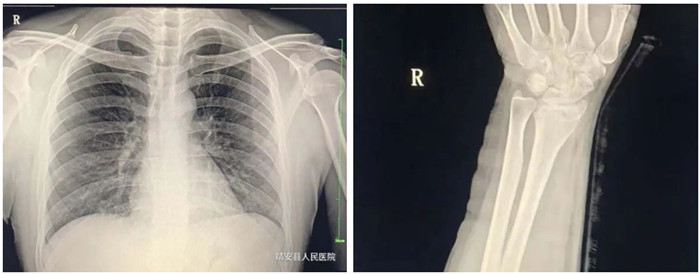

3.胸部

適應癥:氣管支氣管病(支氣管結石及異物等);肺部病變(先天性發育異常、炎癥、結核、腫瘤等);縱膈病變(氣腫、血腫、腫瘤與囊腫等)。

2.脊柱、四肢骨骼及關節

適應癥:骨齡檢查、先天性發育異常、骨缺血性壞死;骨質疏松、骨髓炎、骨腫瘤、骨關節創傷、骨關節結核、骨關節炎性病變、軟組織病變等疾病。